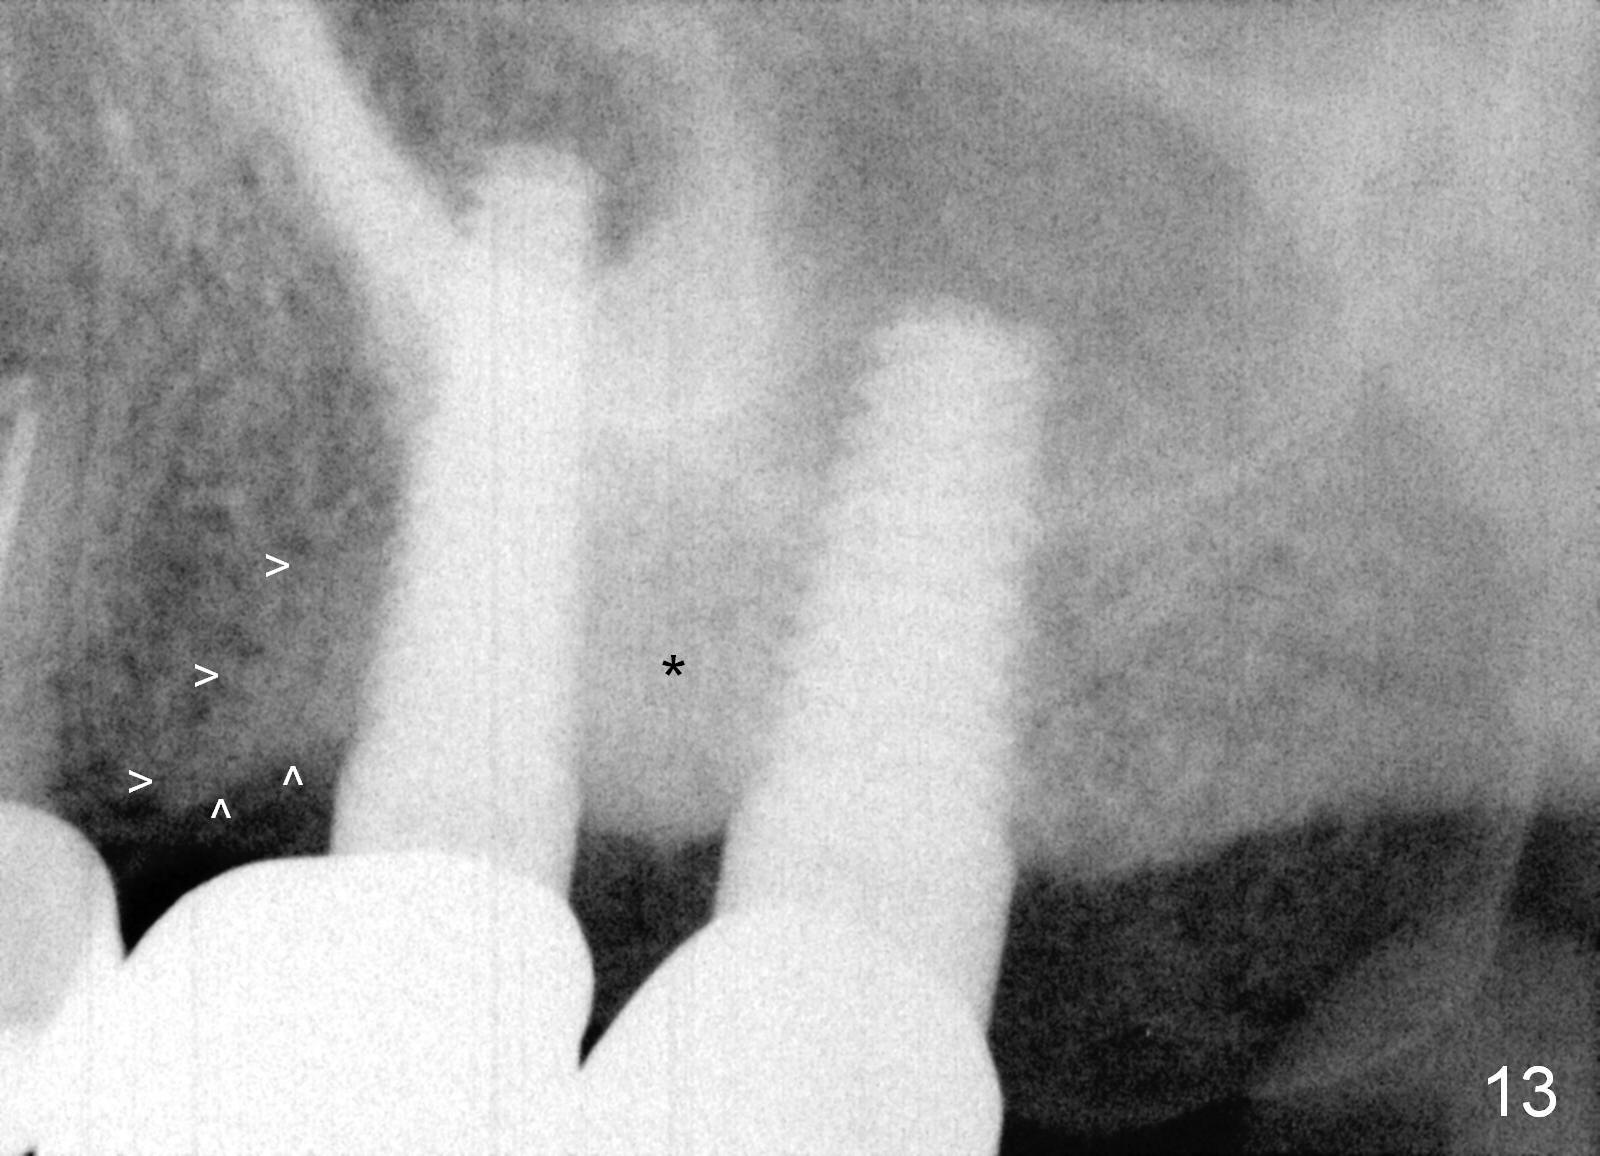

Bone density increases mesially (Fig.13 arrowheads) and distally (*) 1 year 2 months post cementation, 1 year 7 months postop, probably due to the response to the cantilever effect.